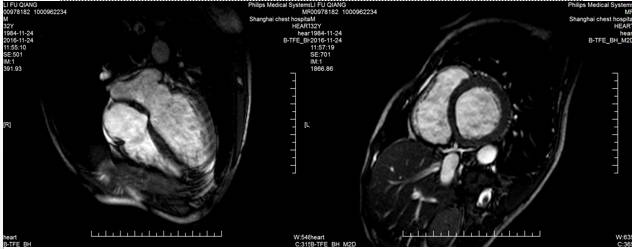

回到我们的病例--心脏MRI

心脏MRI提示

◆2016-11-24心超:

◆左房增大,左室增大;

◆左室壁整体收缩活动度下降,LGE显像提示整个心室壁心肌未见延迟强化现象,故可排除缺血性心肌病

◆LGE显像也未见类似限制性心肌病的特征性心内膜下延迟强化现象。

◆左室内多发条形信号影;LGE扫描未见强化,考虑血栓可能性大。